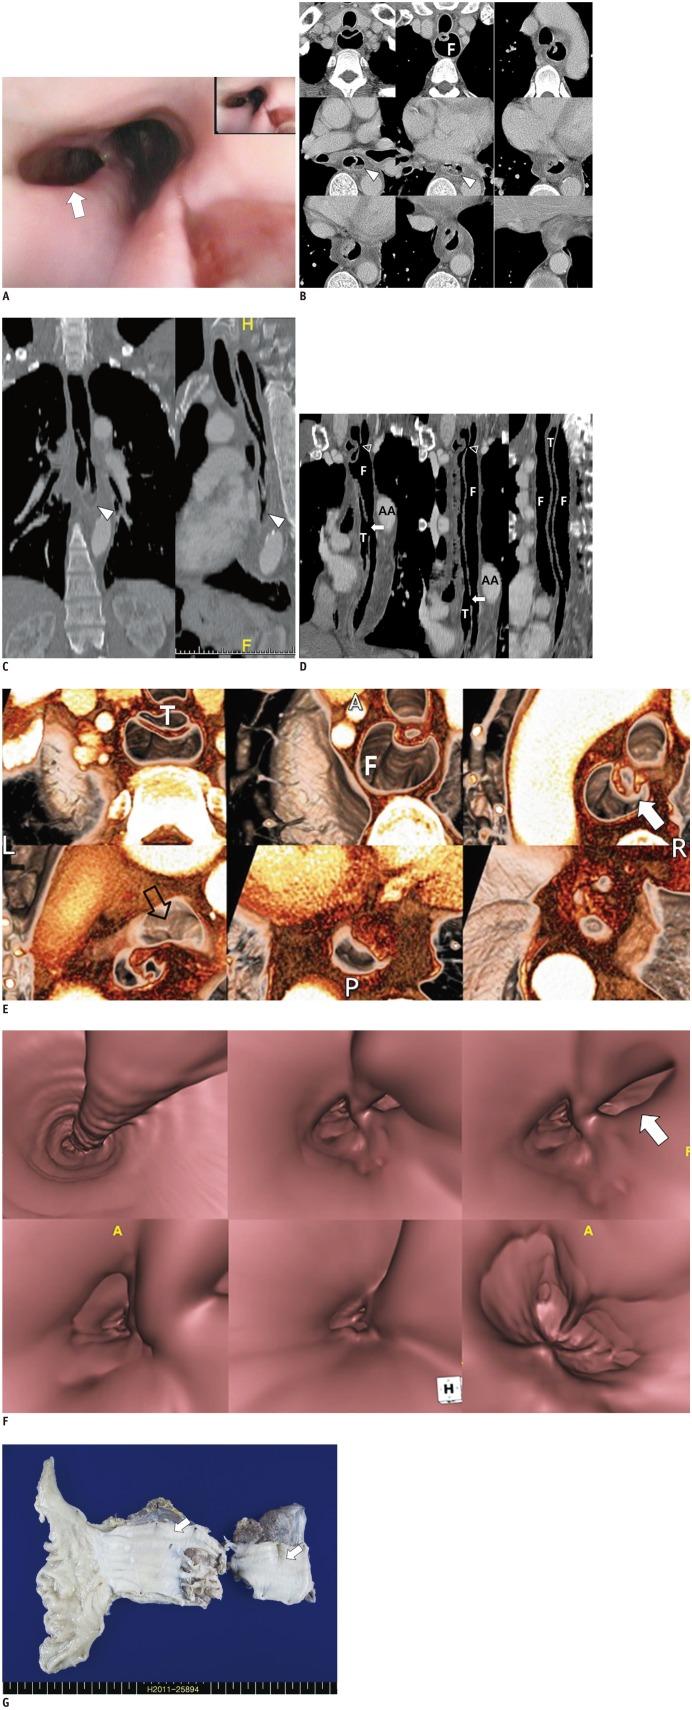

Spontaneous intramural full-length dissection of esophagus treated with surgical intervention: multidetector CT diagnosis with multiplanar reformations and virtual endoscopic display.

Intramural esophageal dissection (IED) is an uncommon disorder characterized by separation of the mucosal and submucosal layers of the esophagus. Iatrogenic intervention is the most common cause of IED, but spontaneous dissection is rare. We report an unusually complicated case of spontaneous IED that involved the full-length of the esophagus that necessitated surgical intervention due to infection of the false lumen. In this case, chest computed tomography successfully established the diagnosis and aided in pre-operative evaluation with the use of various image post-processing techniques.